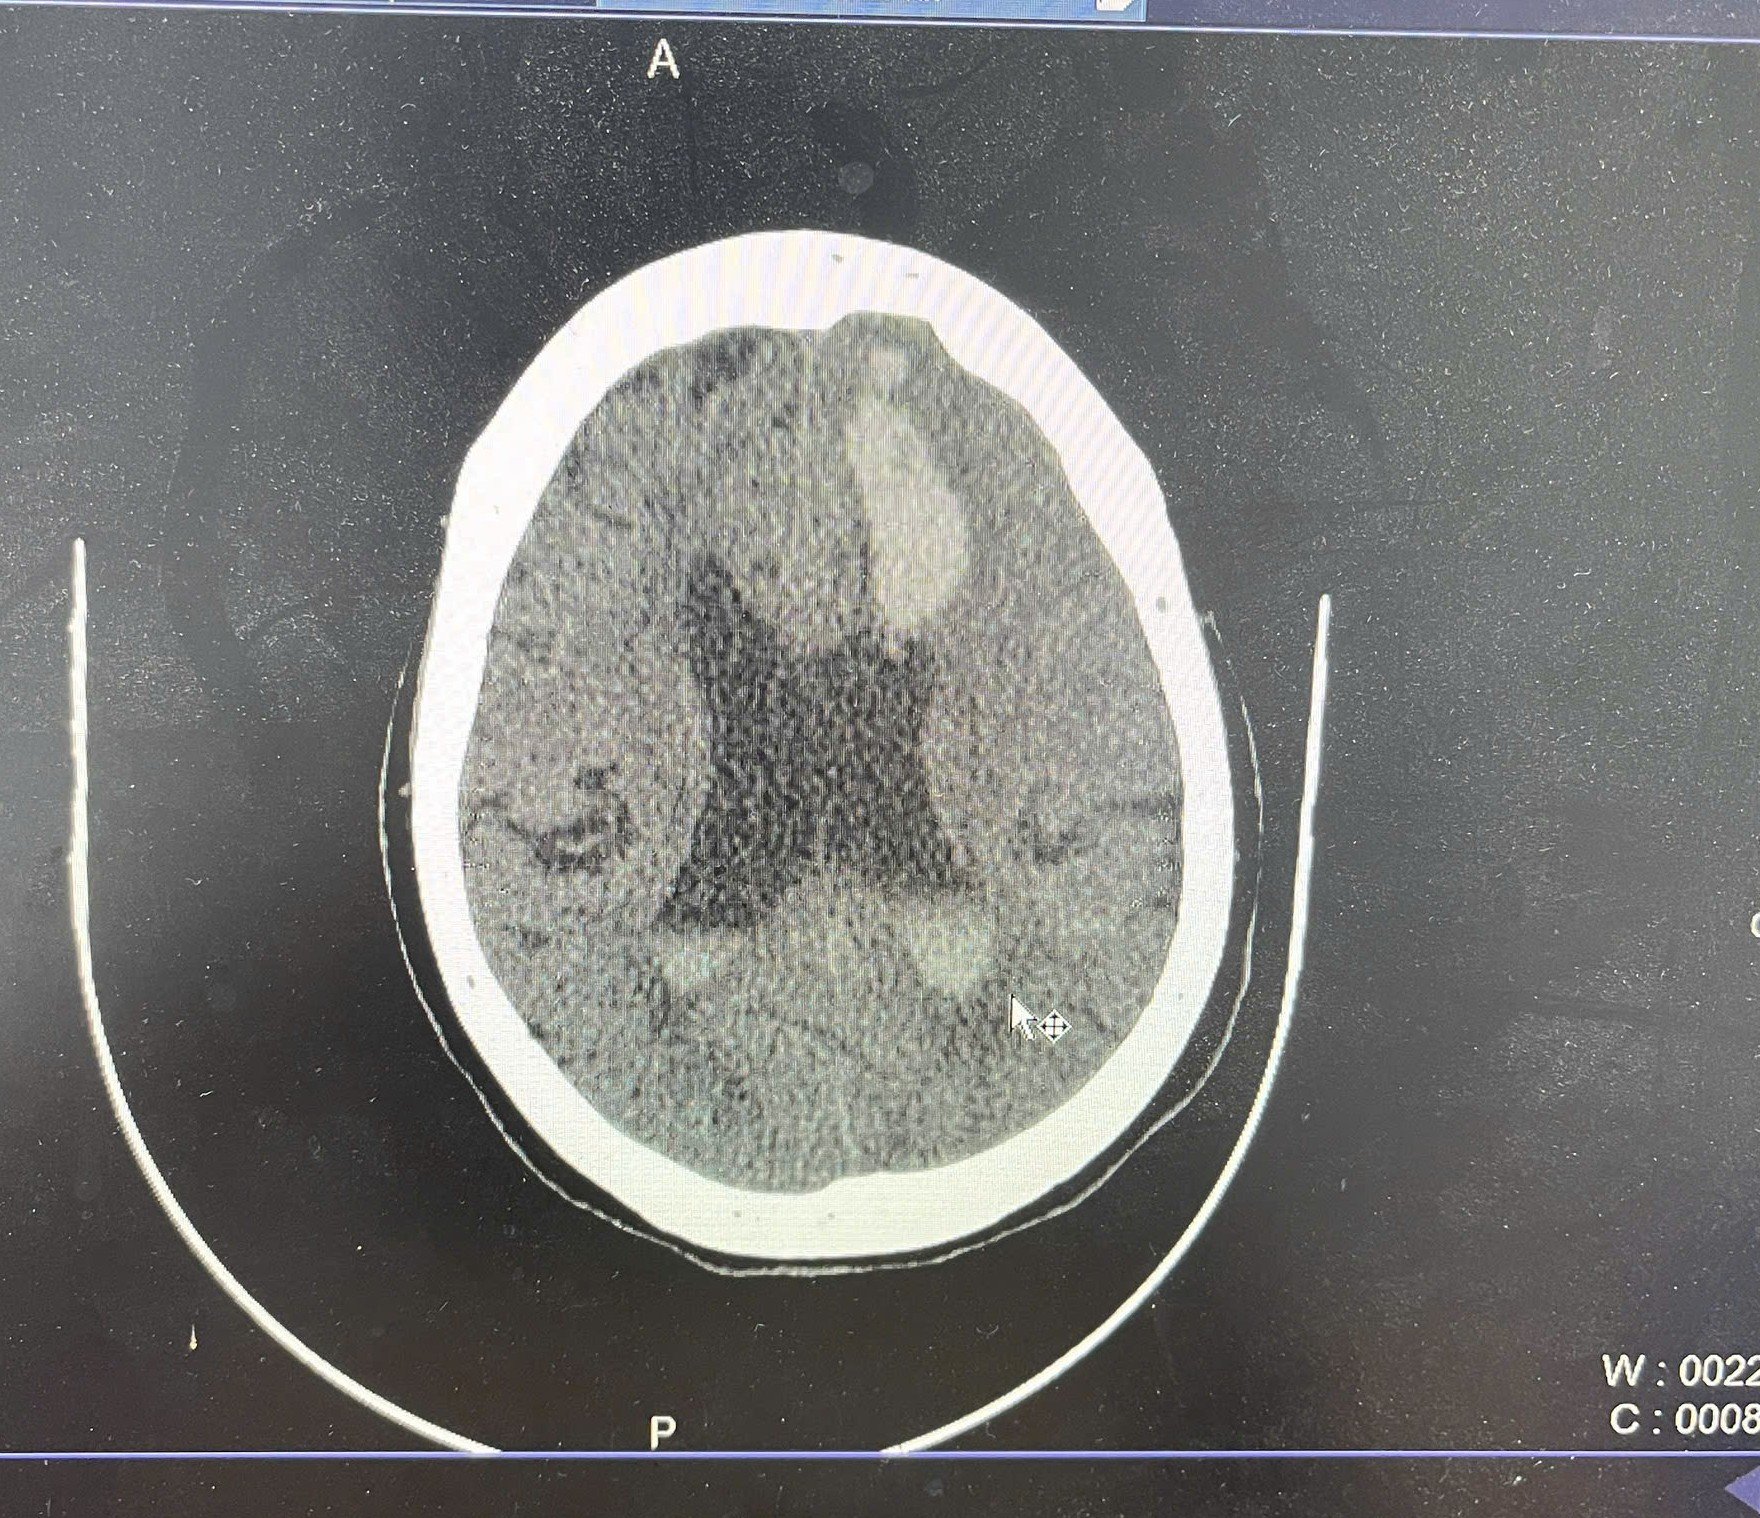

Figure 2. Non-contrast axial CT image at a higher level shows hyperdense hemorrhage in the left periventricular white matter and left lateral ventricle, consistent with intraparenchymal hemorrhage and intraventricular extension. There is surrounding hypodensity representing cerebral edema and rightward midline shift indicating mass effect.

The head CT performed shortly before arrest revealed a large hemorrhage in the left basal ganglia, extending into the lateral and third ventricles, accompanied by diffuse cerebral edema and significant midline shift. These findings were consistent with severe intracranial pathology and an acute elevation in intracranial pressure, leading to brain herniation and loss of circulatory function.